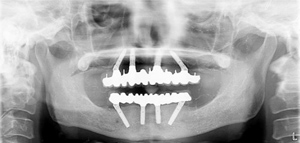

最終補綴物装着

【正面観】

最終補綴物装着後パノラマX線